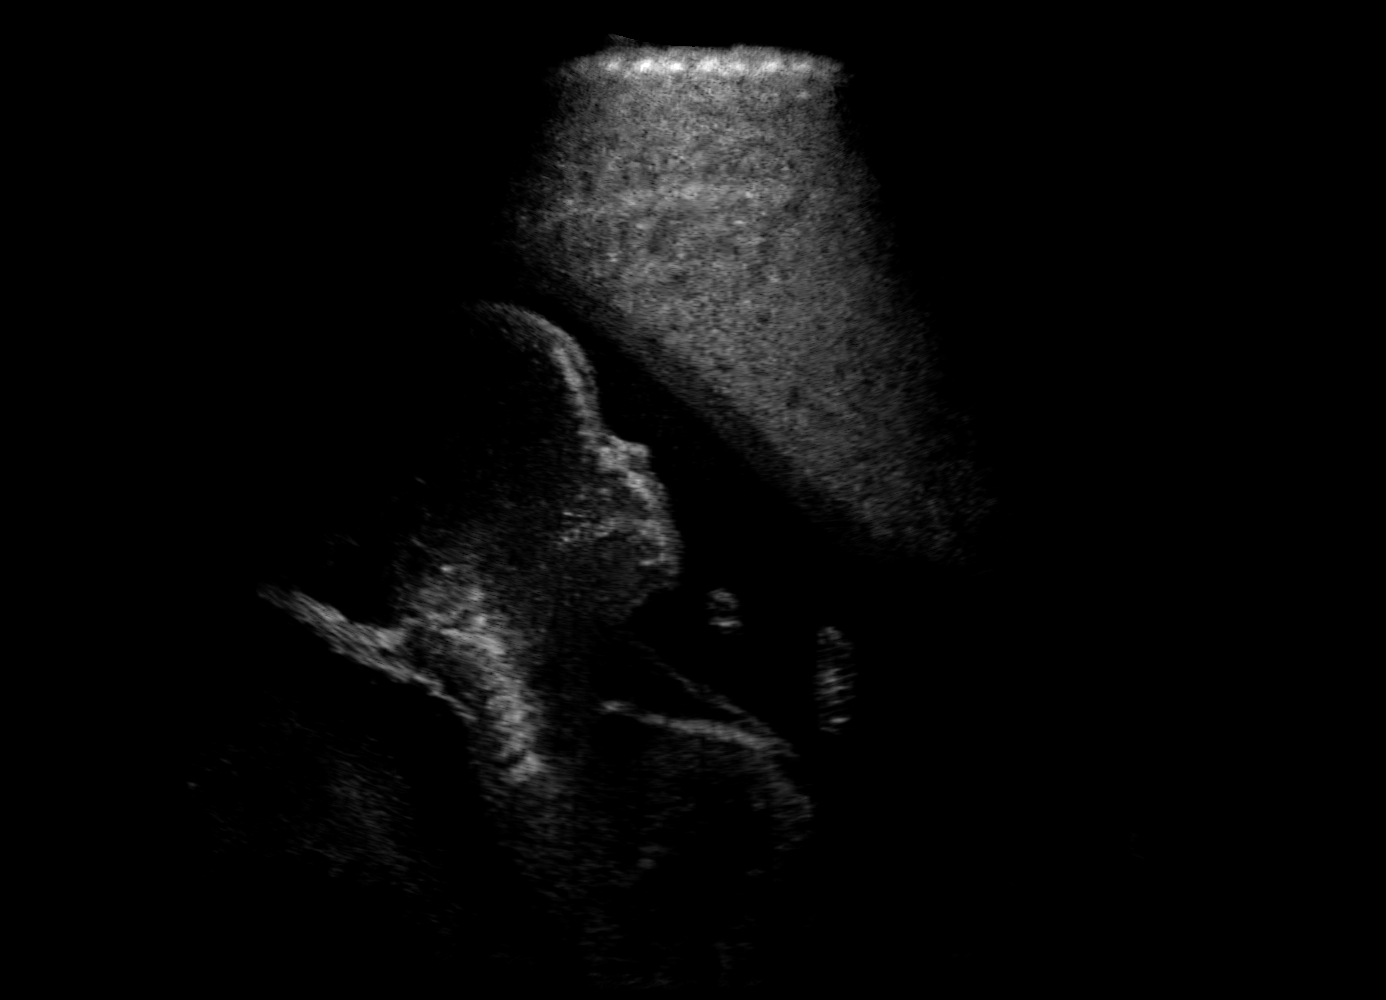

Qualitative evaluation.

Fig. 2 depicts the qualitative results for all the models mentioned above, with arrows pointing at structures relevant to discussion points below. The visual results of the ablated variants of SA2H show substantial quality degradation compared to the full SA2H model, demonstrating the importance of each proposed architectural contribution. Given only segmentation map in the network input, SA2H-att fails to generate acoustic shadows, e.g. those cast by the ribs. Detailed structures such as the cervical vertebrae are blurred out in the SA2H-concat results, which also contain hallucinated structures mainly due to insufficient preservation of input information along the encoding-decoding path. With SA2H-conv, checkerboard artefacts are observed due to the lack of proposed additional stride-1 convolutional layers. SA2H-noise without any explicit noise input is seen to be sub-optimal at generating textural details. The baseline method NSA2H fails to preserve anatomical structures and acoustic shadows in all cases, while the simulated textures also show significant artefacts such as checkerboard patterns. Realism of different simulation aspects may become relevant given different clinical applications and scenarios. For instance, improved structural preservation, e.g. with the hyperechoic bony structures such as the skull and the ribs, of the final model over its ablated variants and NSA2H may prove relevant in fetal head measurements, while the textural improvements facilitating screening fetal organ maturity, e.g. lungs. Compared to the silver-standard model LSA2H with a low-quality rendered image as additional input, SA2H is seen to be on par in structural preservation. Note that shadowing on homogenous regions (e.g. the rib shadowing on the homogenous lung region on the 4th column of Fig. 2) with our proposed method SA2H is represented more faithfully compared to LSA2H, whereas shadows on structurally complex regions (e.g. the skull shadowing around the heart and surrounding tissues on the 3rd column of Fig. 2) are suboptimal with our SA2H. Therefore, one may have to evaluate our method given particular simulation tasks, e.g. its clinical validity for fetal heart exams. However, even with low quality rendered images, LSA2H leads to artificial enhancements of intensities, lack of acoustic shadows, and low-quality textures especially near the probe, for which SA2H yields satisfactory results as illustrated in Fig. 2.

(a) Target

(b) SA2H

(c) SA2H-att

(d) SA2H-concat

(e) SA2H-conv

(f) SA2H-noise

(g) NSA2H

(h) LSA2H